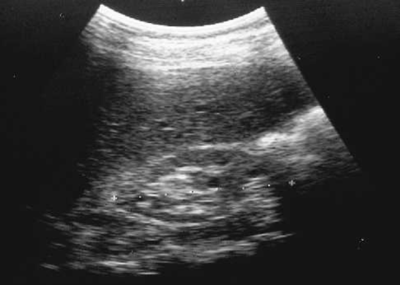

Paciente de sexo femenino, de aproximadamente unos 20 años con antecedentes de Hipertensión. Se presenta Ecografía de riñón. ¿Cuál es el diagnóstico?

Answer

• Riñón en estado normal para un paciente con Hipertensión.

• Una disminución del grosor y un aumento de la ecogenicidad de la cortical posiblemente causado por una insuficiencia renal crónica

• Riñón poliquístico acompañado por un alargamiento del riñón.

• Cancer renal.